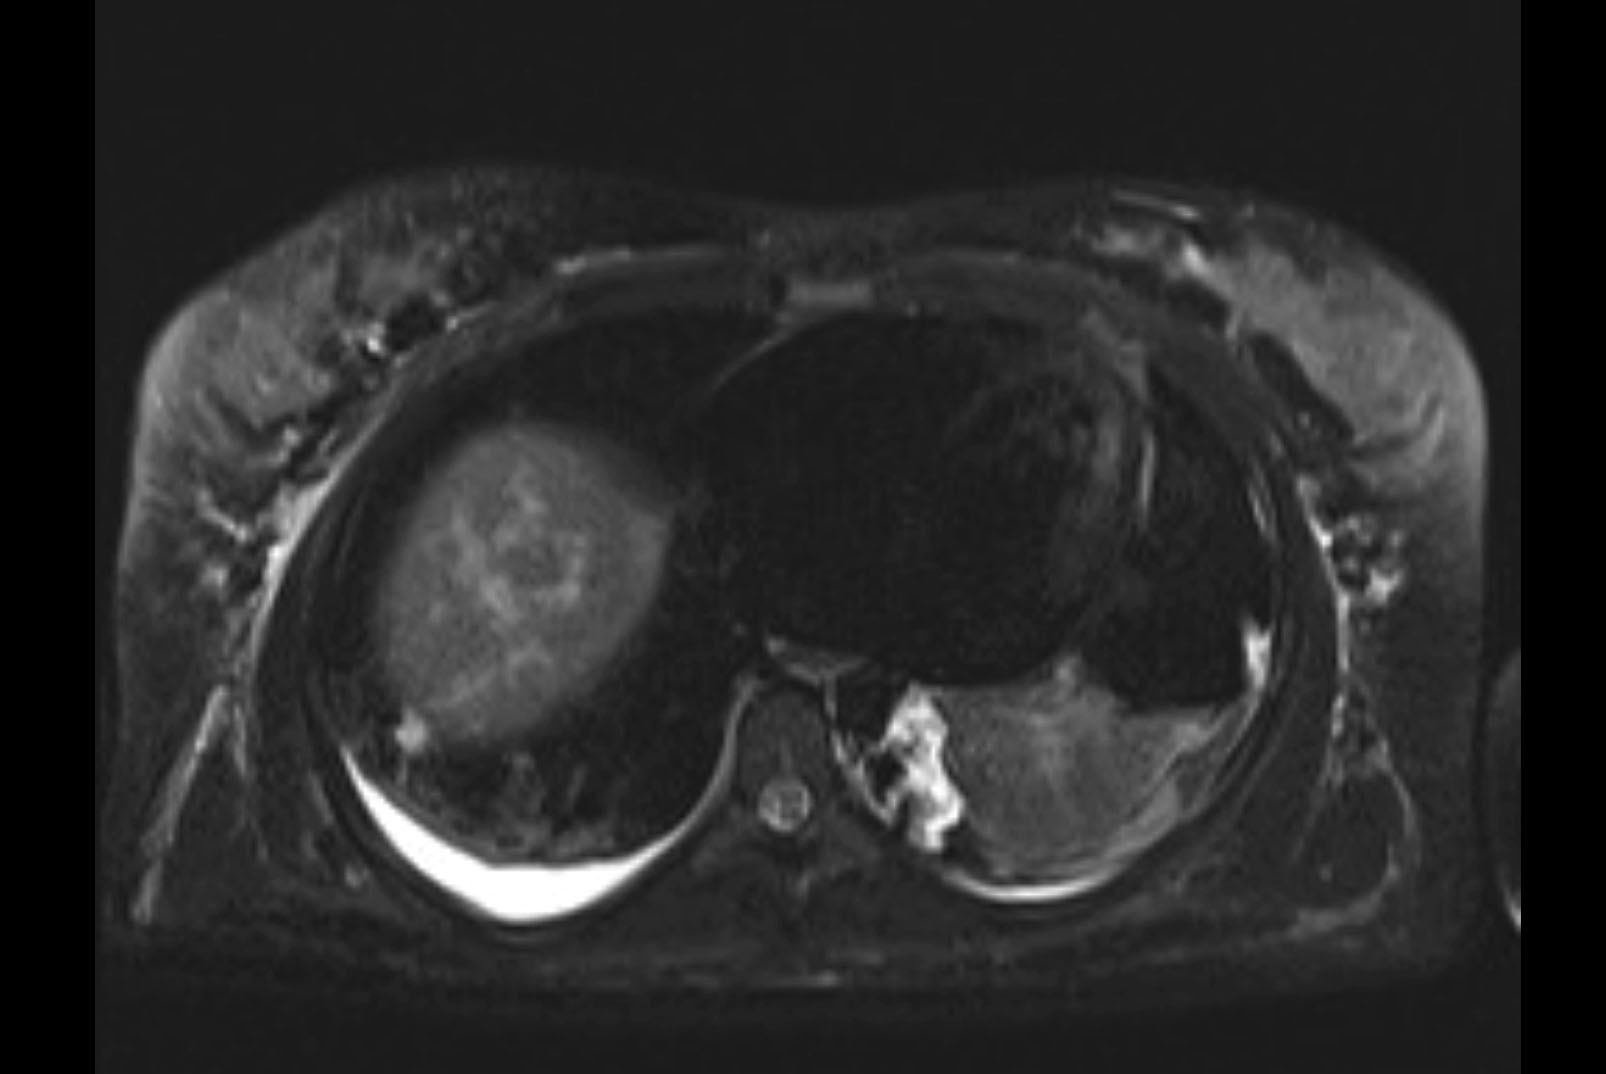

Imaging Analysis

Look through the patient's CT scan to identify any areas of concern for the necessary procedure.

MRI T2

Based on initial findings, which issue(s) would you be most concerned about?